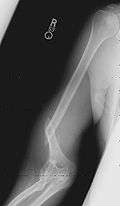

Associated injury

Arm wrestling puts enormous torque/torsion stress on the upper arm's humerus bone to a degree seen in few other physical activities.[5] Most people's bones are not accustomed to being significantly stressed in this direction, and injuries can occur. The arm typically fails because of a diagonal break at or below the midpoint between the shoulder and the elbow.